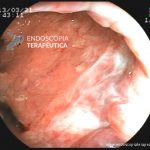

- Doença de Crohn em remissão – cicatriz